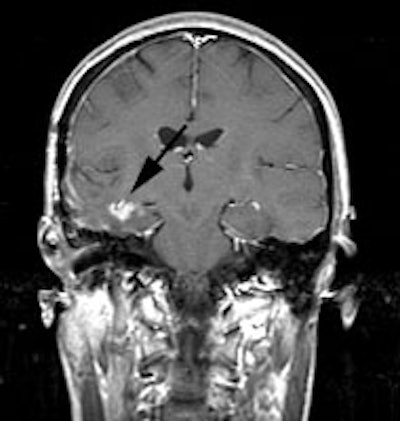

CNS recurrent glioma: The patient below had a history of a right temporal lobe glioma. The lesion had been treated with surgery and radiation. A follow-up MR exam demonstrated areas of enhancement in the right temporal lobe on post-gadolinium images (black arrows). MR spectroscopy was inconclusive. The FDG PET exam demonstrated a hypermetabolic focus in the area of MR signal abnormality consistent with recurrent glioma (white arrows). |